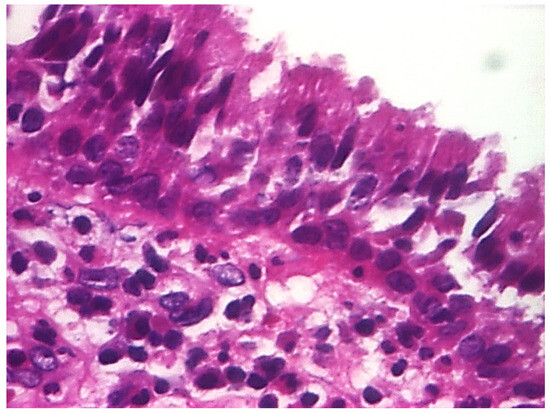

| Histopathologic Aspects | Number of Patients |

|---|---|

| Cholesteatom | 276 |

| Polip | 180 |

| Tympanic membrane mucosa chamber, epithelium with apocrine-like cells, and chronic inflammatory infiltrate | 128 |

| Cell Types | Percentage |

| Lymphocytes T | 42.55% |

| Lymphocytes B | 31.45% |

| Macrophages | 26.00% |